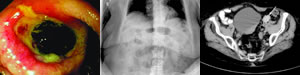

体格检查:意识不清,血压75/30 mmHg,脉搏90次/分,腹部查体未见异常,直肠检查提示无黑便。实验室检查:血红蛋白下降,尿素氮升至21.9 mmol/L 。对患者进行液体复苏后,行上消化道内镜检查,镜下发现十二指肠球部有一病变(图1)。

图1 十二指肠球部病变的内镜影像

图2 腹部X线平片可见扩张的小肠肠袢。

图3 CT可见乙状结肠内异位胆石(箭头所指)。

上消化道镜检提示溃疡,有血管显露,未见活动性出血,相邻处可见嵌顿结石。在内镜下行溃疡周边肾上腺素液浸润,并采用双极电凝将显露血管凝固。患者住院期间无再出血。

内镜术后第3天,患者出现恶心、呕吐症状。腹部X线平片提示,小肠扩张,有阻塞像(图2)。内镜术后第6天,腹部计算机体层摄影(CT)可见,乙状结肠内存在一个大小约为27×19 mm的胆石(图 3)。该患者无胆囊炎征象,胆石是通过胆囊十二指肠瘘落入肠道,随后移行至大肠。